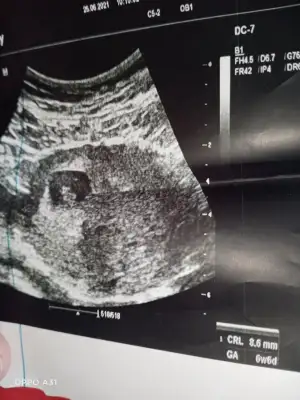

Benim bebeğime de bakar mısınız 9 buçuk haftalık. Belki erken ama bir yorumunuz olursa diye merak ediyorumEn iyi 11 12 13 haftalar olmalışimdilik erkek yönünde ama yanıltabilir dediğim haftalar olmalı

Şimdilik erkek yönünde ama en iyi 11 12 13 haftalar olmalı tekrar USG paylasinBenim bebeğime de bakar mısınız 9 buçuk haftalık. Belki erken ama bir yorumunuz olursa diye merak ediyorum

6haftalik 10 ve 11haftalik görüntüsü